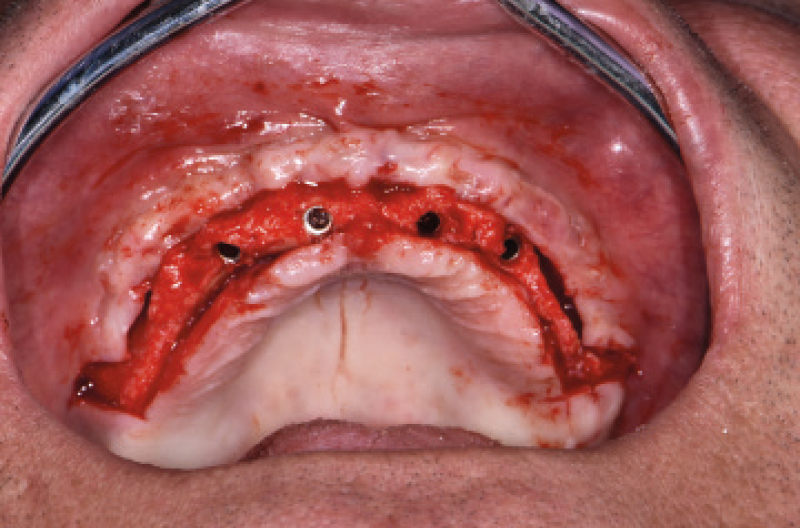

Ho riaperto il mascellare superiore con un lembo a spessore parziale palatino e con scarichi solo distali per limitare al minimo il trauma allŌĆÖosso perimplantare; dopodich├® ho scelto i monconi MUA pi├╣ idonei, tutti GH 1,5 mm uno diritto, tre angolati a 15┬░ e due angolati a 25┬░. Una volta parallelizzati, ho attivato i monconi MUA negli impianti e avvitato gli adattori Conic per trasformarli in monconi MUA-Conic. Dopo aver suturato il lembo, ho attivato le cappette Fixed sui monconi MUA-Conic e poi si ├© proceduto alla ribasatura della protesi opportunamente scaricata in corrispondenza dei monconi MUA-Conic. Durante la procedura intraorale di inglobamento delle cappette Fixed, la protesi si ├© autocentrata in occlusione con la protesi conometrica fissa provvisoria inferiore. Infine la protesi ├© stata rifinita, riposizionata in bocca e attivata (Figg. 30-37). A distanza di un mese entrambe le Toronto provvisorie sono state rimosse e ribasate per un migliore condizionamento del tessuto gengivale (Fig. 38).

Fig. 34 – Vista occlusale dei monconi MUA-Conic